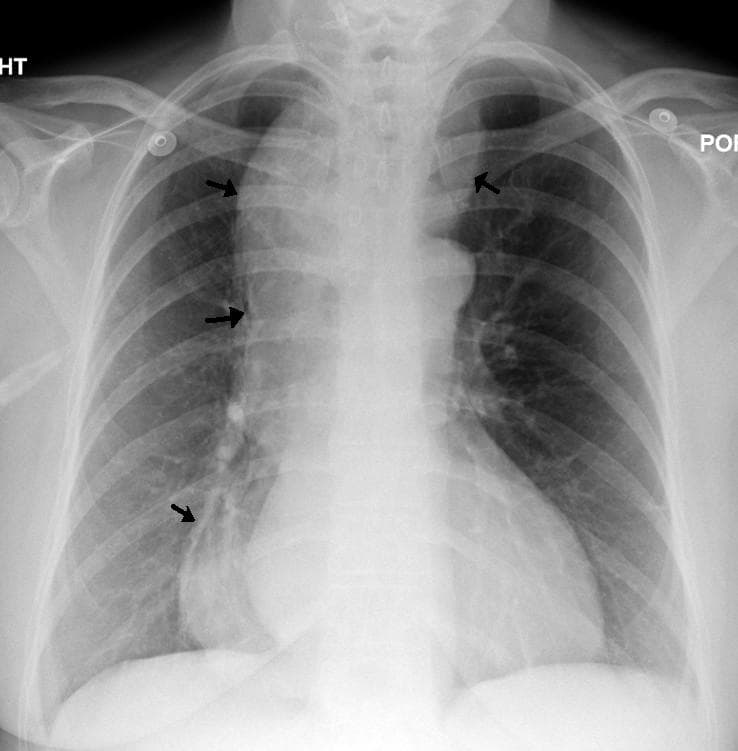

L'achalasie, qui signifie « difficulté à se relâcher » , également appelée cardio-spasme ou mégaœsophage, est une maladie rare de cause inconnue consistant en un trouble moteur primitif de l'œsophage. Elle est définie par l’absence du péristaltisme œsophagien et par une absence de relaxation ou relaxation incomplète du sphincter inférieur de l'œsophage (SIO). L'atteinte a été décrite pour la première fois par Thomas Willis en 1674. Le taux d'incidence est de pour par an, à peu près comparable selon les pays. La prévalence est de 1 pour . Au Royaume-Uni, environ en sont atteintes. L'âge de survenue s'étend de , l'incidence augmentant avec l'âge. Cette affection touche aussi bien les hommes que les femmes. Il existe des prédispositions génétiques, en particulier chez les porteurs de l'HLA-DQ1, de certains allèles du VIPR1 (récepteur 1 du peptide vasoactif intestinal), du promoteur de l'interleukine 10. Il peut aussi se retrouver dans le cadre d'un syndrome MIRAGE (chromosome 7, gène SAMD9) ou d'un syndrome Allgrove (triple A) Le sphincter du bas œsophage est innervé et commandé par des neurones. Ces derniers sont en nombre réduit ou absents lors de l'achalasie. Le mécanisme de cette disparition pourrait être auto immunitaire. Le sphincter inférieur de l'œsophage (SIO) restera inerte et empêchera l'évacuation du liquide oesophagien. La dysphagie est une sensation de gêne ressentie au moment d'avaler. Elle se manifeste chez 99 % des patients. La régurgitation des aliments non digérés est présente chez des malades. On note un amaigrissement de chez 64 % des patients en moyenne. Des douleurs thoraciques peuvent survenir après les repas chez des malades. Il peut s'agir de brûlures rétrosternales ou pyrosis. Une toux peut être présente pour un tiers des malades, en particulier la nuit ou en position couchée. Ces signes ne sont pas spécifiques, expliquant un diagnostic parfois très retardé pouvant atteindre plusieurs années. Le score d'Eckardt est utilisé pour évaluer la gravité des symptômes en fonction d'un grade.